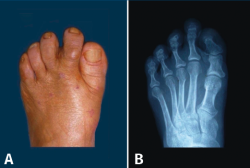

Figura 7. Neanderthal foot o pie ancestral de Dudley Morton. A: aspecto clínico; B: imagen radiológica.

En los primates arborícolas, existen pues a nivel del antepié una serie de características anatómicas también presentes en el HV en la especie humana: pronación del primer metatarsiano, ángulo I-II muy aumentado, hipermovilidad del primer radio y oblicuidad de la articulación cuneometatarsiana. Todas estas características son la justificación de la hipótesis de un factor atávico en muchos casos de HV.